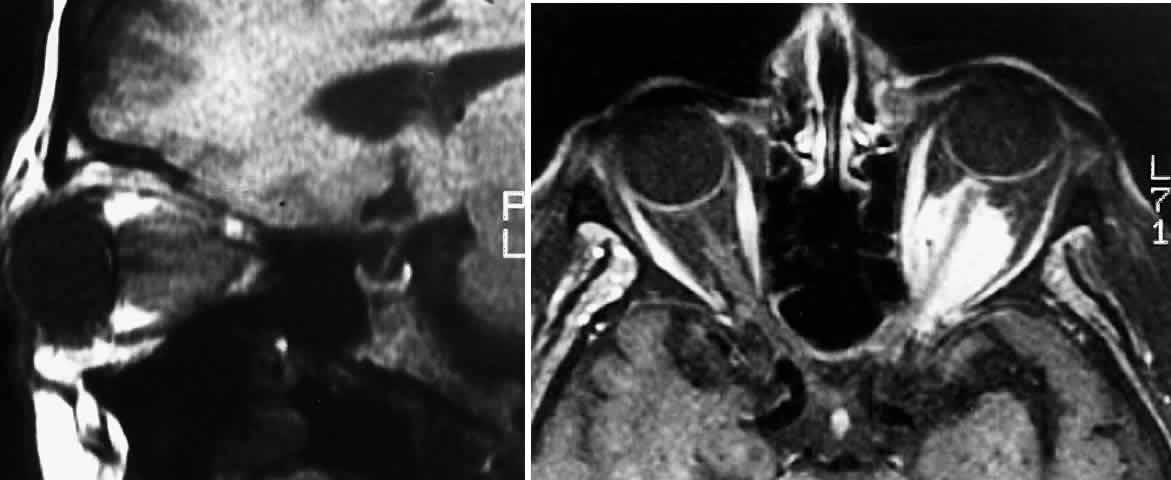

gliomas, Wisoff17 noted three patterns characterized by patient age: Children less than 2 years of age manifested visual failure, macrocephaly, and

failure to thrive. The majority of published cases of optic pathway gliomas describe some component of chiasmal involvement; almost half of these chiasmal gliomas extend into the adjacent hypothalamus or the third ventricle.3 Gliomas involving the optic nerve alone make up approximately 25% of all optic pathway gliomas.3 It is uncertain whether gliomas with both chiasmal and hypothalamic involvement originate in the chiasm or the hypothalamus before involving adjacent neural tissue.18,19 In patients with neurofibromatosis type 1 (NF-1), tumors can often be multifocal.20–22 In a major review, the sex distribution for all optic pathway gliomas was equal.3 A predominant number of patients with gliomas confined to the optic nerve were female (67%).3,18,23–25 Although some reports have demonstrated a greater prevalence of chiasmal gliomas among males,24 and others among females,26 an extensive analysis of the literature3 has failed to show any association between patient sex and gliomas occurring at this location. Although these tumors may be more common among whites, a racial association has not been substantiated in the literature.13 The majority of patients with childhood optic gliomas present with some degree of visual loss. The pattern of visual loss can usually be described as painless and insidious, consistent with a chronic optic neuropathy. However, a precipitous loss of vision simulating optic neuritis has been described when hemorrhage occurred within the tumor.27 A relative afferent pupillary defect is usually present, and there may be acquired dyschromatopsia. Chiasmal glioma patients tend to present with bilateral visual loss.18,23,25,28,29 Although almost three quarters of all optic glioma patients in a large retrospective study had visual acuities described at presentation to be worse than 20/40,3 some gliomas seem to exist with clinically normal visual function and may demonstrate only mild abnormalities identified by visual evoked responses.30 Depending on the location of the tumor in the visual pathway, visual field examination may demonstrate a variety of patterns, including generalized constriction, cecocentral and central scotomas, altitudinal defects, and bitemporal hemianopia. Since the potential exists for chiasmal glioma to involve the optic nerves and tracts, almost any type of visual field defect is possible.31–35 Because the function of the nerve fibers coursing through involved tumor areas may be unaffected, an absence of bitemporal hemianopia should not be interpreted as an indication of freedom from chiasmal involvement.4 Fundus examination demonstrates some component of optic atrophy in more than one half of described cases.3 The presence of disc edema may be noted in patients with intraorbital optic nerve gliomas as well as in patients with chiasmal gliomas. Edema from chiasmal tumors may be secondary to either anterior tumor extension involving the optic nerves, or from extension into surrounding neurologic structures with ventricular obstruction and resultant papilledema. Enlargement of the optic disc in optic glioma patients has also been reported.36 Direct tumor pressure on the posterior aspect of the globe may produce a hypermetropic refractive change and retinal striae.4 Although more commonly seen in optic nerve sheath meningiomas, optociliary shunt vessels have also been reported. Other vascular features resulting from glioma compression of the central retinal vein include central retinal vein occlusion, venous stasis retinopathy, and neovascular glaucoma.37,38 With violation of the arterial blood supply to the eye, anterior segment ischemia may be noted.39 Patients with NF-1 may have ocular colobomas, microphthalmos, or macrophthalmos.40 Proptosis is most common in patients with intraorbital tumors, although it can sometimes be observed in patients with concomitant chiasmal and intraorbital involvement3 (Figs. 1 and 2). Proptosis can be the presenting sign in glioma patients, and may even precede visual loss.13 Pain associated with the proptosis is not characteristic of optic gliomas.4 Minimal to severe proptosis, generally nonpulsatile and axial in nature, has been described, but it is typically in the range of 2 to 4 mm. Severe proptosis may jeopardize the health of the globe; it may also be a major cosmetic problem. The tumor itself is usually not palpable. Standardized A-scan examination of optic nerve gliomas demonstrates echograms of regular, homogeneous, low-to-medium reflectivity. On B-scan examination, large optic nerve gliomas appear as fusiform masses replacing the optic nerve void.41 In contrast to optic gliomas, meningiomas are typically irregular in structure and demonstrate higher internal reflectivities.41,42 The 30° test is usually negative when performed on gliomas because of the solid infiltration of the nerve; however, positive tests have been noted, suggesting perioptic subarachnoid fluid surrounding the tumor.42

As a consequence of asymmetric or unilateral visual loss, sensory-induced strabismus may develop.18,28 Gliomas interfere with ocular motility by causing direct mechanical restriction4 and paralytic strabismus. Damage to the ocular motor nerves may occur directly by invasion of the tumor at the orbital apex, or secondarily by raising intracranial pressure. Vertical, horizontal, rotary, and see-saw nystagmus has been reported, and may even precede visual loss as an initial sign of a glioma. Consequently, children with spasmus nutans or monocular or asymmetric nystagmus may need neuroimaging and careful follow-up in order to exclude a chiasmal glioma.43–47 Patients with chiasmatic and hypothalamic involvement may develop endocrinologic manifestations, including diabetes insipidus, panhypopituitarism, girdle-type obesity, and dwarfism.48 If hypothalamopituitary function is impaired, children may exhibit a precocious puberty in association with growth hormone deficiency.49,50 Depending on the extent of the glioma in the hypothalamic region, neurologic manifestations can include epilepsy, hemiparesis, and the diencephalic syndrome. With obstruction of the third ventricle or foramen of Monro, hydrocephalus may occur with manifestations of lethargy, headache, and vomiting. |